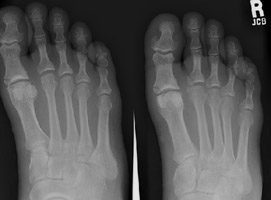

- Click on the image for a larger versionAAP and oblique radiographs of the foot. These reveal several fractures. There is a fracture of the distal aspect of the first metatarsal as well as fractures of the proximal aspects of the proximal phalanges of digits one and two.